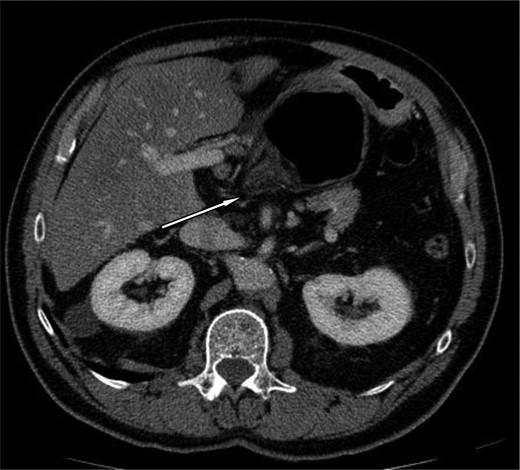

A 69-year-old patient presented to our emergency room with progressive dull abdominal pain and distension without nausea, vomiting or change in bowel habits. Physical examination showed pain with moderate guarding in the right upper and lower quadrants. A plain abdominal X-ray and a CT scan were performed. Radiological findings suggested the diagnosis of an internal hernia through the epiploic foramen and containing the right colon with important distension of the caecum (Fig. 1). Surgical exploration was then performed using an open approach. At laparotomy, we found an internal herniation of the caecum and the entire ascending colon through the foramen of Winslow (Figs 2 and 3). After hernia reduction, multiple patchy areas of caecal necrosis were observed (Fig. 4). A formal right hemi-colectomy was therefore performed. The postoperative recovery was uneventful.

Axial section demonstrating the hernia through the foramen of Winslow.